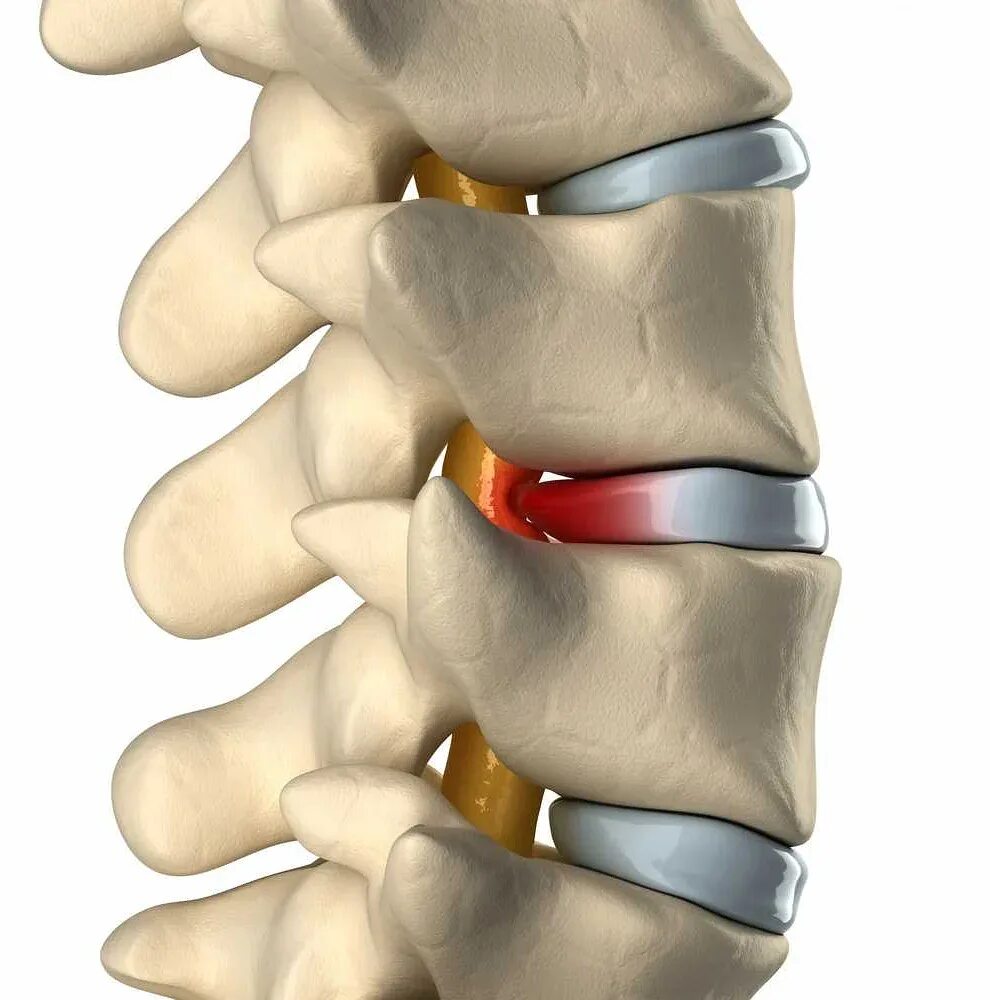

Как лечить грудную грыжу позвоночника